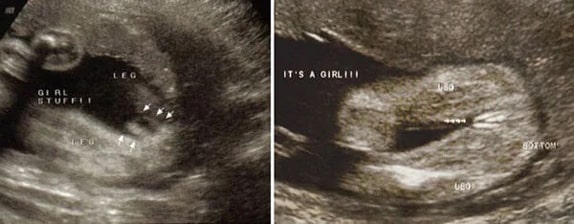

29 Haftalık Kız Bebek Ultrason Görüntüsü

30 Haftalık Kız Bebek Ultrason Görüntüsü

31 Haftalık Kız Bebek Ultrason Görüntüsü

32 Haftalık Kız Bebek Ultrason Görüntüsü

33 Haftalık Kız Bebek Ultrason Görüntüsü

34 Haftalık Kız Bebek Ultrason Görüntüsü

35 Haftalık Kız Bebek Ultrason Görüntüsü

36 Haftalık Kız Bebek Ultrason Görüntüsü